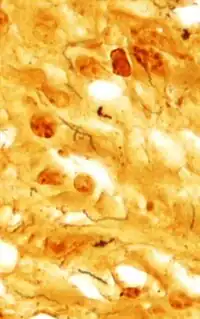

Coloration de Dieterle mettant en évidence Treponema pallidum, l'organisme qui cause la syphilis.